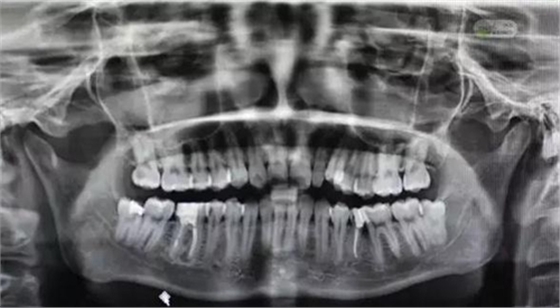

圖2.術(shù)前全景片檢查:48近中有致密充填影像,雙根、牙根與下頜管重疊。